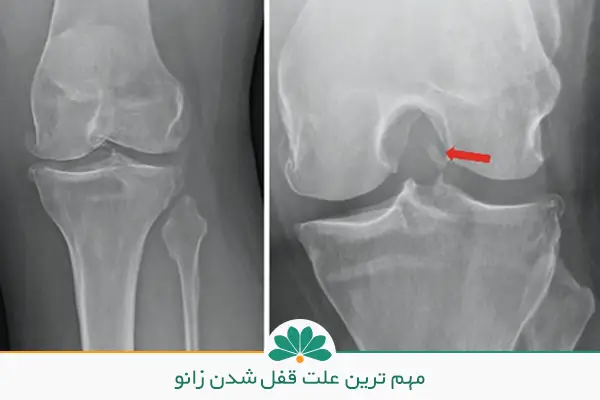

· آسیب مینیسک: پارگی یا گیر افتادن مینیسک زانو میتواند حرکت مفصل را مختل کند.

· مشکلات مکانیکی داخل مفصل: گاهی قطعات کوچک غضروف یا استخوان جدا شده و مانع حرکت طبیعی زانو میشوند.

در این شرایط ممکن است پزشک برای بررسی دقیقتر از روشهای تصویربرداری مانند MRI استفاده کند تا مشکلاتی مانند پارگی مینیسک یا آرتروز پیشرفته مشخص شود.